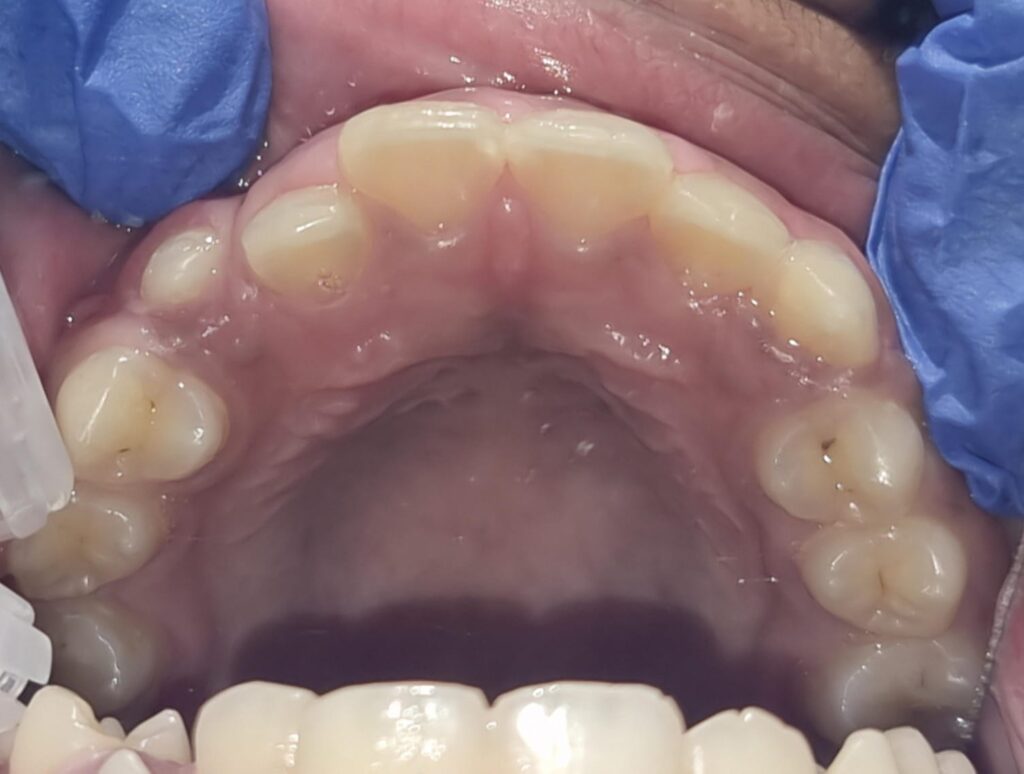

37) Jad – Upper and lower crowding and both laterals are palatally placed. – Upper treatment is completed.